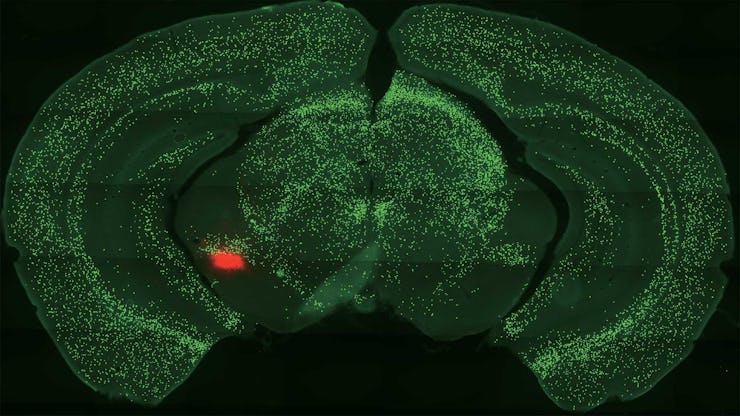

In an experiment involving mice, researchers at Cold Spring Harbor Laboratory found that cells in the amygdala fire in distinct ways in response to various learned cues.

Then they conducted neuroimaging to see how those specific central amygdala neurons — known as somatostatin-expressing central amygdala neurons (somatostatin is a peptide hormone that regulates the endocrine system) — behaved in response to the various sounds. These particular neurons comprise about half of the central amygdala, which is why the team took a close look at those cells’ activity.